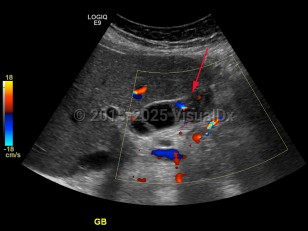

Imaging Studies image of Gallbladder carcinoma - imageId=7884800. Click to open in gallery.  caption: 'Ultrasound with color Doppler demonstrating mass within the gallbladder with internal vascularity.'

Ultrasound with color Doppler demonstrating mass within the gallbladder with internal vascularity.